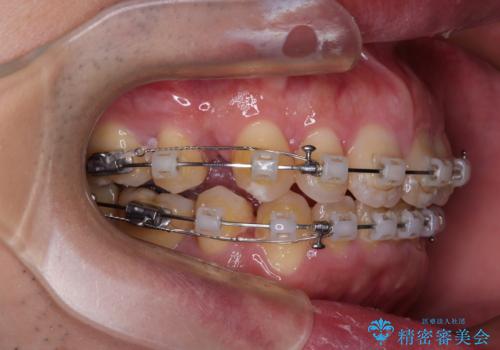

- クリアブラケット

- 2年3ヶ月

- 口が閉じられないとのことで来院された患者様です。

顎先に力を入れないと唇が閉じきれない口元であったので、上下左右の第一小臼歯4本を抜歯して、ワイヤー装置にて矯正治療を行うこととしました。